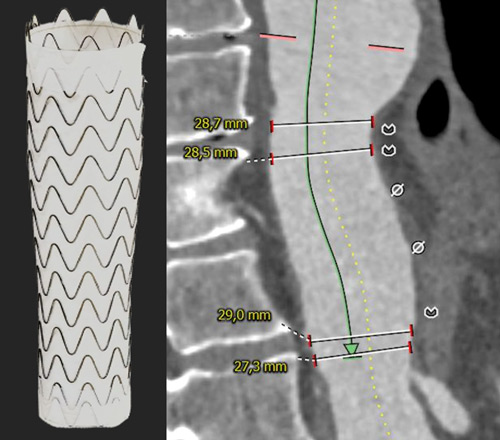

Distal optimisation and future treatment option

- Further extension of the 37 x 200 mm Gore® TAG® Conformable with a large diameter tapered 37/31 x 150 mm TAG® Conformable

- Reduction of the risk of a distal stent graft–induced new entry (dSINE) and improved adaptation to the patient’s anatomy.

- Adaptation to the patient’s individual anatomy by extending the 37 mm TBE with an additional 37 mm TAG® Conformable with long overlap.

- Further extension of the 37 mm TAG® Conformable with Large Diameter Tapered TAG® Conformable to match the distal aortic diameter.